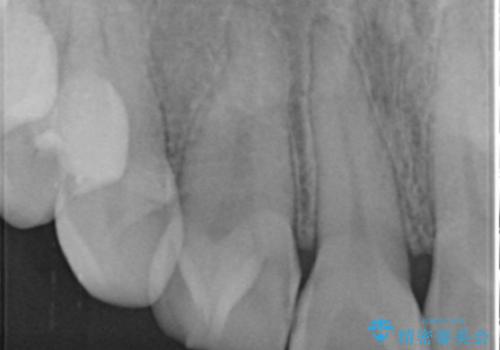

- 1週間ほど前に自転車で転倒して前歯をぶつけた後、歯の色が変わっていることが気になり受診された方です。診察の結果、失活及びエナメル質に多数の亀裂が認められたため、根管処置およびセラミッククラウンによる治療を行いました。元々右上2番目の歯の形が気になっていたとの事で、左右対称の形に近づけるように補綴しました。

左上1番目の歯は失活していませんでしたが、歯の表面に多数の亀裂が認められました。患者様のご希望により、前歯3本をまとめて補綴処置することとなりました。土台となる歯質の色が異なる状態でしたが、熟練した技工士さんの技術により3本とも同じ色味になるように仕上げていただきました。色味、形態ともに自然な被せ物に大変喜んでいただけました。